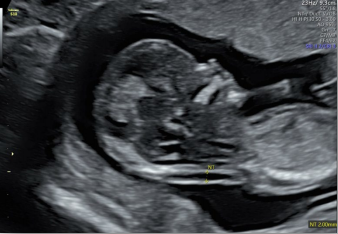

Voluson內(nèi)置自動化技術(shù)幫助醫(yī)生精簡工作流程,減少擊鍵次數(shù);同時提高了測量的一致性和可重復(fù)性,推動檢查效率。

生長指標半自動測量

在合適切面下,可自動識別測量臨床所需的胎兒雙頂徑,頭圍,腹圍,股骨長和肱骨長度等多個參數(shù)。